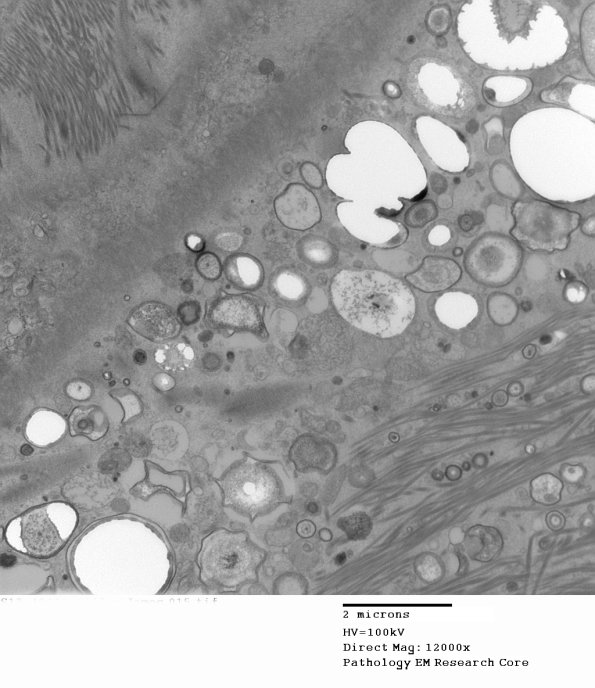

Higher magnification of perineurial mineralizations.